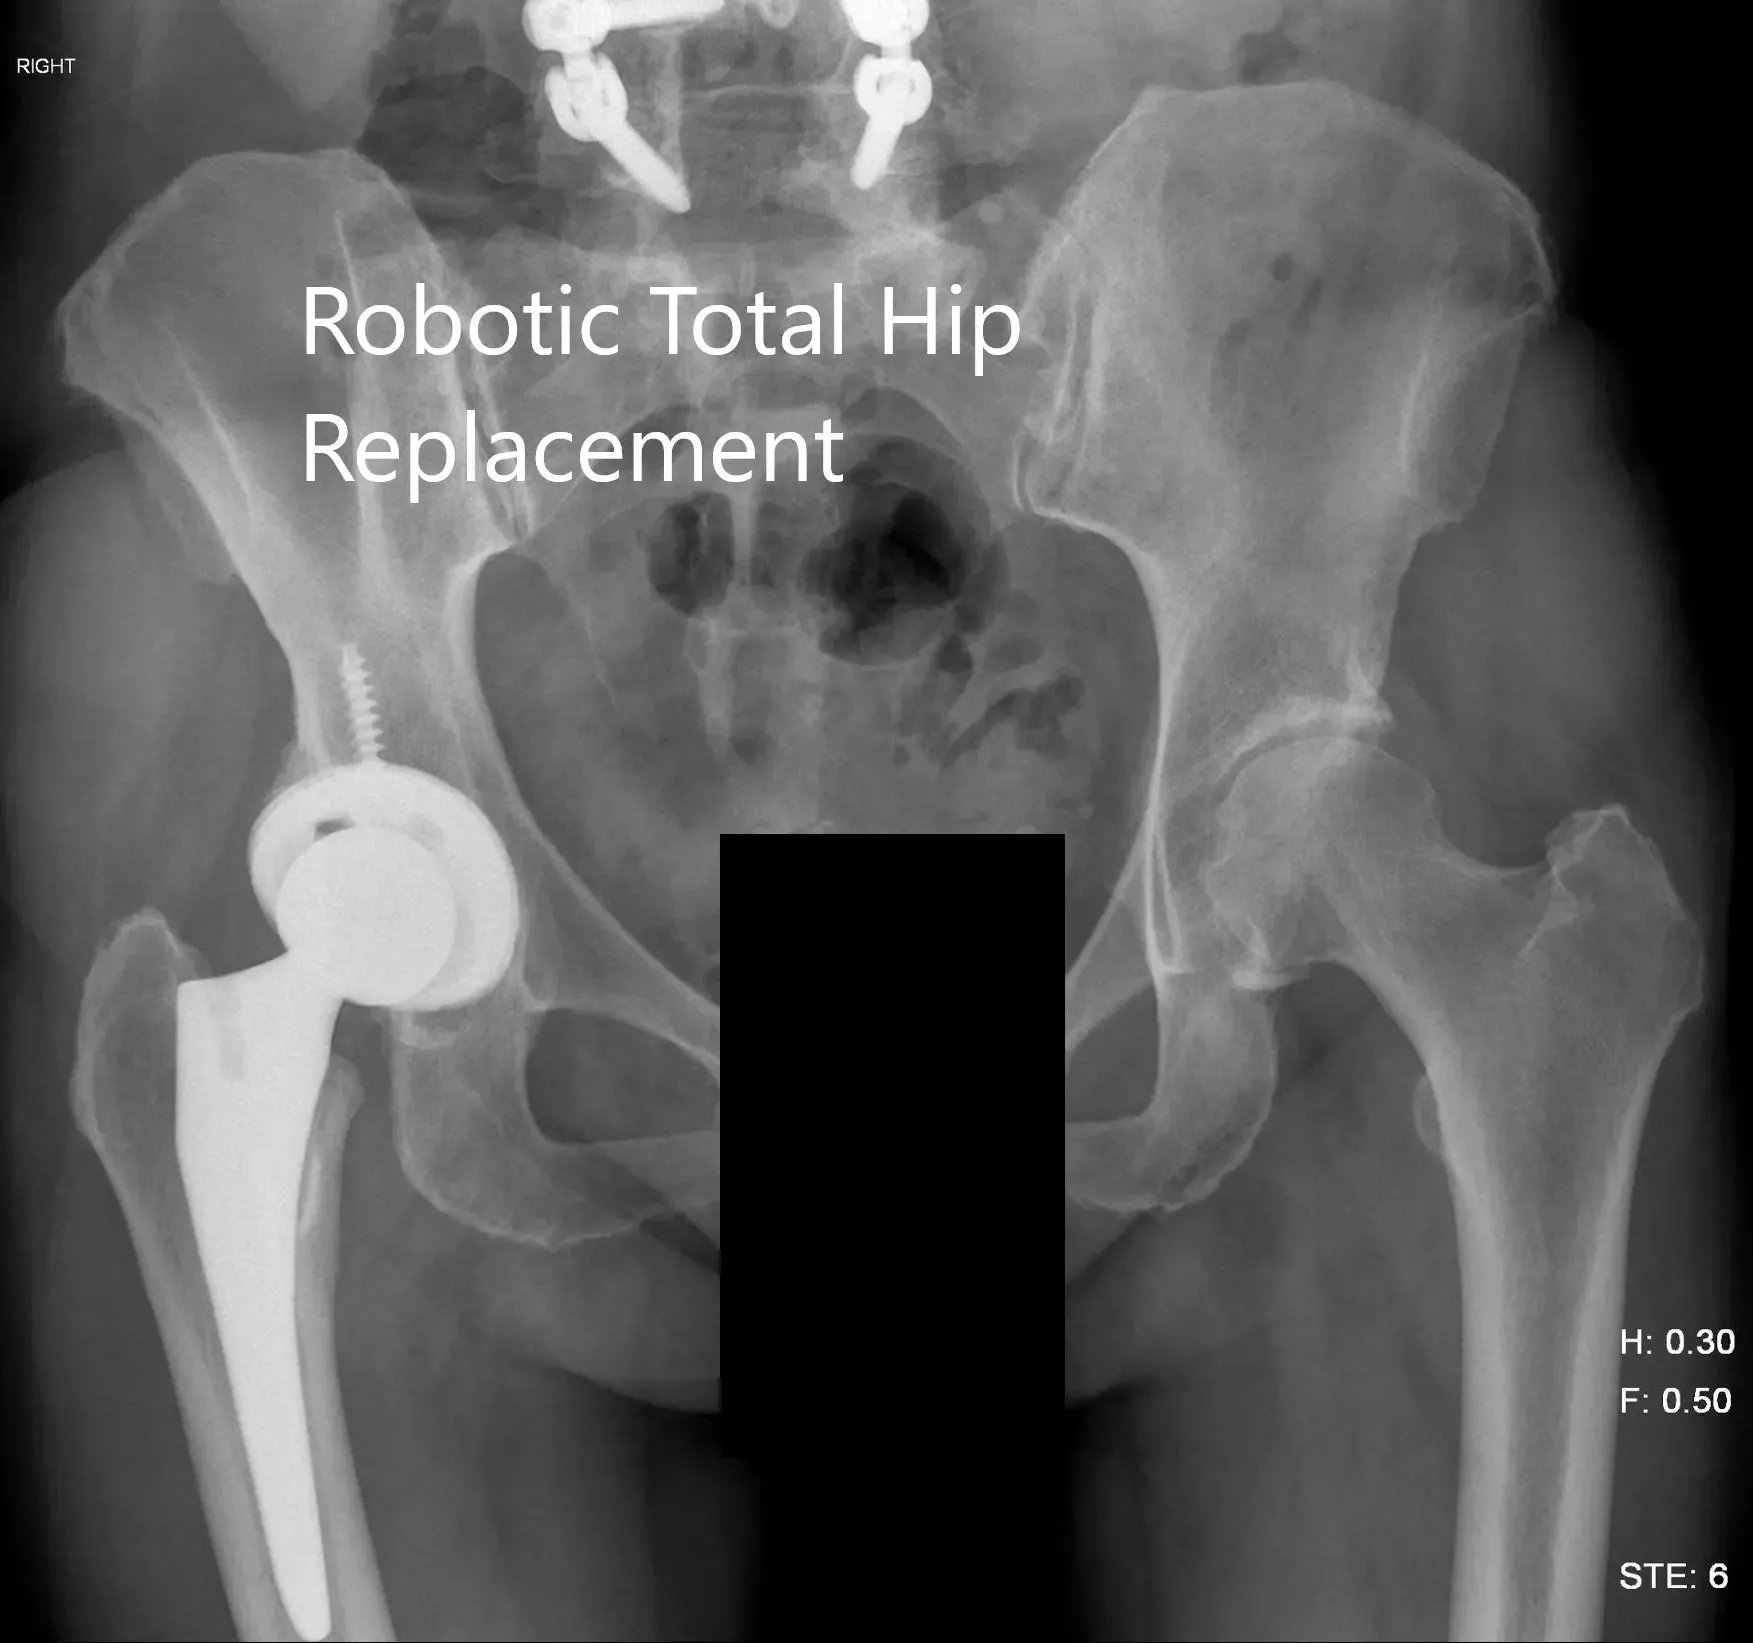

Postoperative X-ray of the pelvis showing AP view.

IMPLANTS USED: Tritanium cluster shell 52-mm with 6.5-mm x 30-mm screw with a Trident shell. Zero degrees poly with a 127-degree stem with a ceramic head, outer diameter 32-mm minus 4.